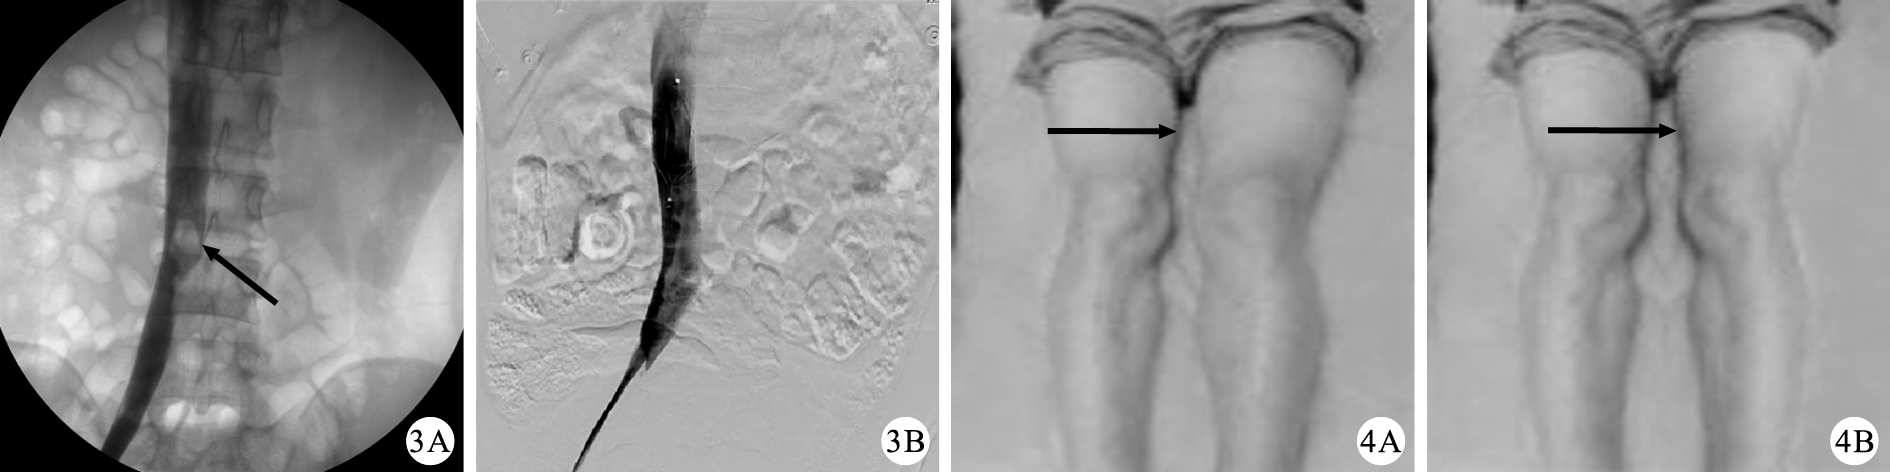

首先于外踝處行小切口暴露出小隱靜脈,穿刺小隱靜脈,經小隱靜脈置入4 F導管鞘,然后推造影劑明確小隱靜脈走形并進一步明確穿刺靜脈確為小隱靜脈,繼而用J形超滑導絲牽引4 F單彎導管向近心端前行,邊前進邊推造影劑,尋找小隱靜脈匯入腘靜脈的匯入口,將導管通過小隱靜脈、腘靜脈、股淺靜脈、股靜脈插入髂靜脈內,再用長度為260 cm硬滑導絲交換出4 F單彎導管,將溶栓導管沿導絲置于漂浮血栓下端,側孔埋于血栓內。經溶栓導管持續泵入尿激酶(60~80)×104 U/d,同時口服華法林2.5~3 mg/d(依據患者每日檢測凝血功能調整劑量),1周后行DSA觀察血栓溶解情況,調整溶栓導管位置并持續溶栓治療。溶栓12 d后再行DSA觀察血栓溶解情況,并根據血栓溶解情況及濾器上附著血栓情況酌情取出下腔靜脈濾器。

隨訪16例患者,其中14例患者來我科復查,另有2例患者無法聯系。對該14例患者進行隨訪,隨訪時間6個月,術后6個月復查下肢血管彩超,下肢深靜脈CDFI值較出院時未升高,行多普勒檢查示雙下肢股淺靜脈、腘靜脈均呈間斷音,提示下腔靜脈血流通暢。測量雙下肢髕骨下10 cm處周徑較出院時未出現增粗,提示下肢腫脹情況未見加重,無下肢靜脈曲張表現(圖 4)。復查肺動脈CT提示未見明顯肺動脈栓塞征象。